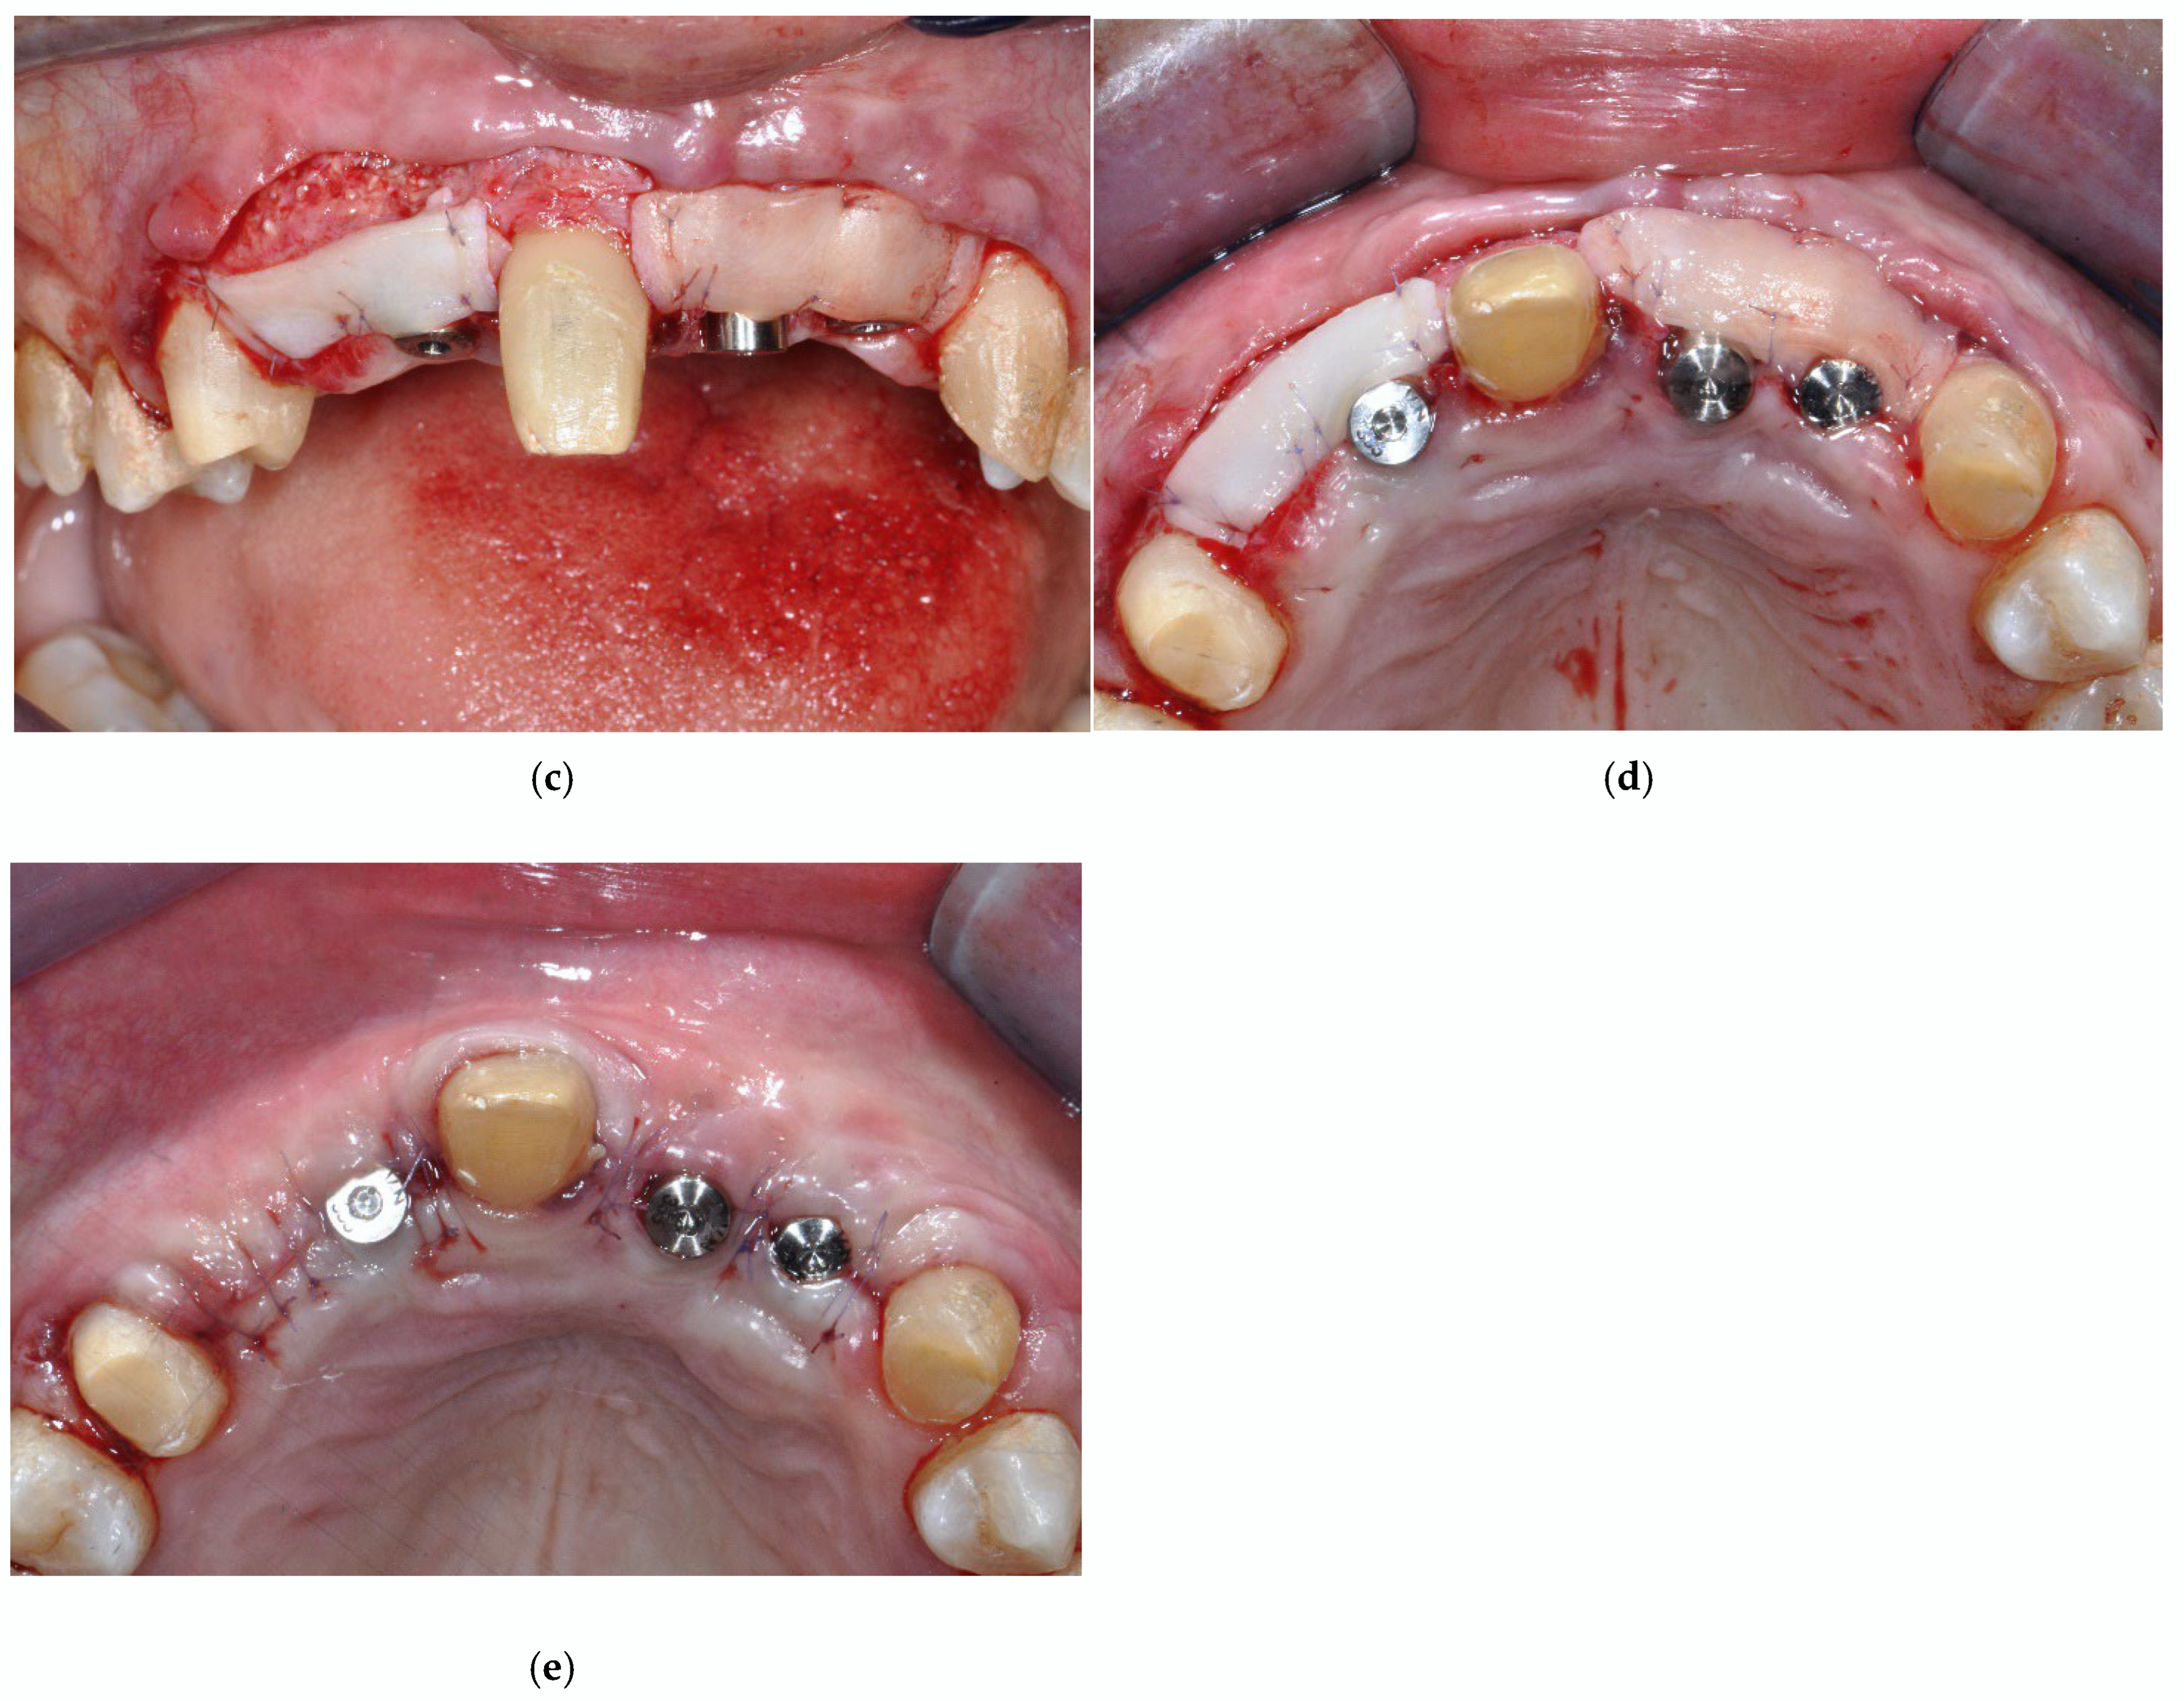

2.2. Surgical Procedure